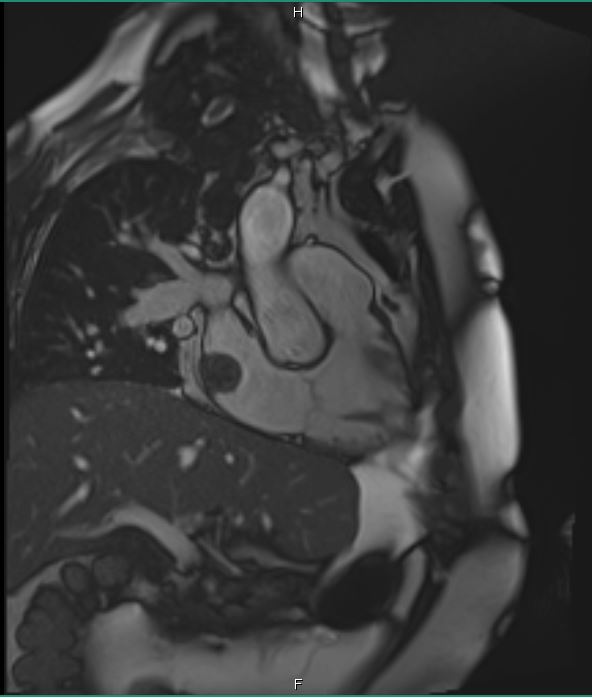

Cardiac MRI was performed on January 3, 2018, which revealed a large 2.5 × 2.9-cm lobular, fairly sessile mass in the right atrium. Without evidence of tissue destruction to suggest a malignant process, the lesion was suggestive of either myxoma or hematoma due to marked contrast uptake (which is seen less often with myxomas) (Figure 1).

Figures 1A-G. Cardiac MRI findings of a large, lobular, fairly sessile mass in the right atrium, measuring 2.5 x 2.9 cm, suggestive of either myxoma or hemangioma.